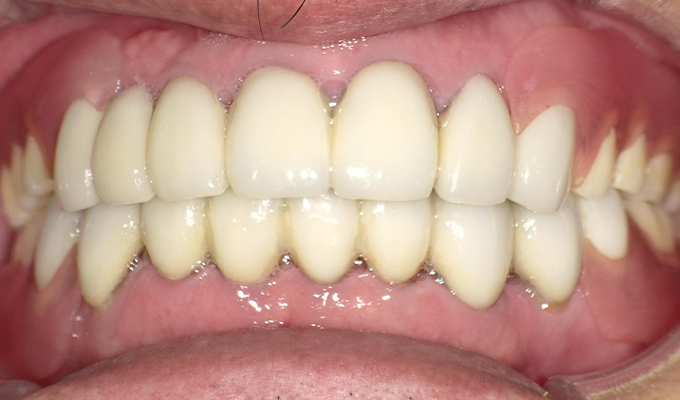

case2ジルコニアクラウンの症例

初診時(2013年)

初回メンテナンス時(2014年)

最新メンテナンス時(2024年)

- 初診時の年齢

- 50代女性(2013年)

- 主訴

- 右上奥の銀歯が取れた。この際悪いところはすべて治療したい。

- 治療内容

- 取れてしまった銀歯の根が割れていたため抜歯しブリッジの治療になりました。

「せっかくならきれいにしたい」と八重歯になっている右上下の犬歯を抜きジルコニアブリッジを入れました。

セルフケアもしっかりやっていただいているので10年経過してもきれいな状態を維持されています。